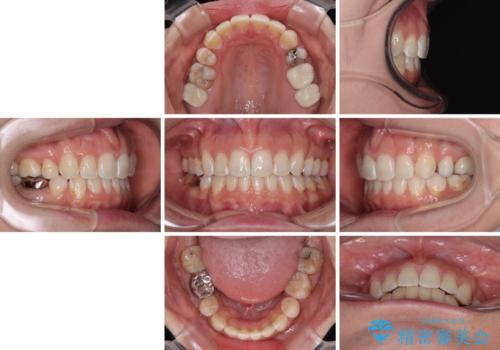

出っ歯と奥歯のむし歯 ワイヤー装置での抜歯矯正とセラミック治療

- 口元の突出感と奥歯のむし歯を気にして来院された患者様です。

奥歯の虫歯は事前に矯正治療用の仮歯に置き換えて矯正治療を行い、装置除去後にセラミッククラウンにて補綴治療を行うこととしました。

通常は上下左右の第一小臼歯4本を抜歯することになりますが、左側下顎の第二小臼歯は既に根管治療をされており、予後が良くないとのことでこの歯を抜歯し、ワイヤー装置にて矯正治療を行うこととしました。

第二小臼歯抜歯はイレギュラーな治療手段であり、治療期間が延びる傾向にありますが、予定よりも早い2年間で終えることができました。